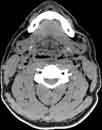

Visible Human male: Sectio transversalis 1219

CT

NMR

Pd T1 T2